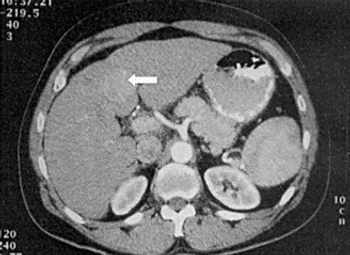

A recent study found that radiation therapy was effective for the palliation of painful spinal metastases in patients with hepatocellular carcinoma.